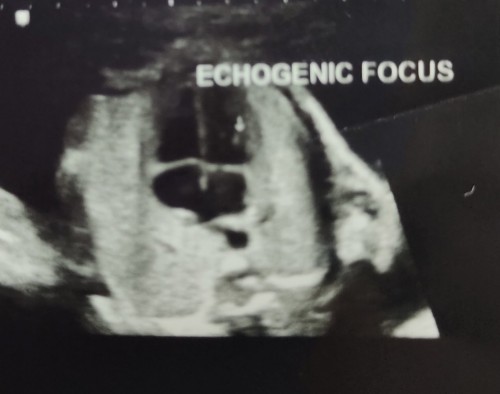

Echogenic Focus

Tadi saya buat detail scan 22 weeks, and find out pasal echogenic focus ni. Please ada sesiapa yg tahu pasal ni atau lalui benda mcm ni? Risau saya 🥺#pleasehelp #firstbaby #advicepls #1stimemom #bantusharing #ingintahu